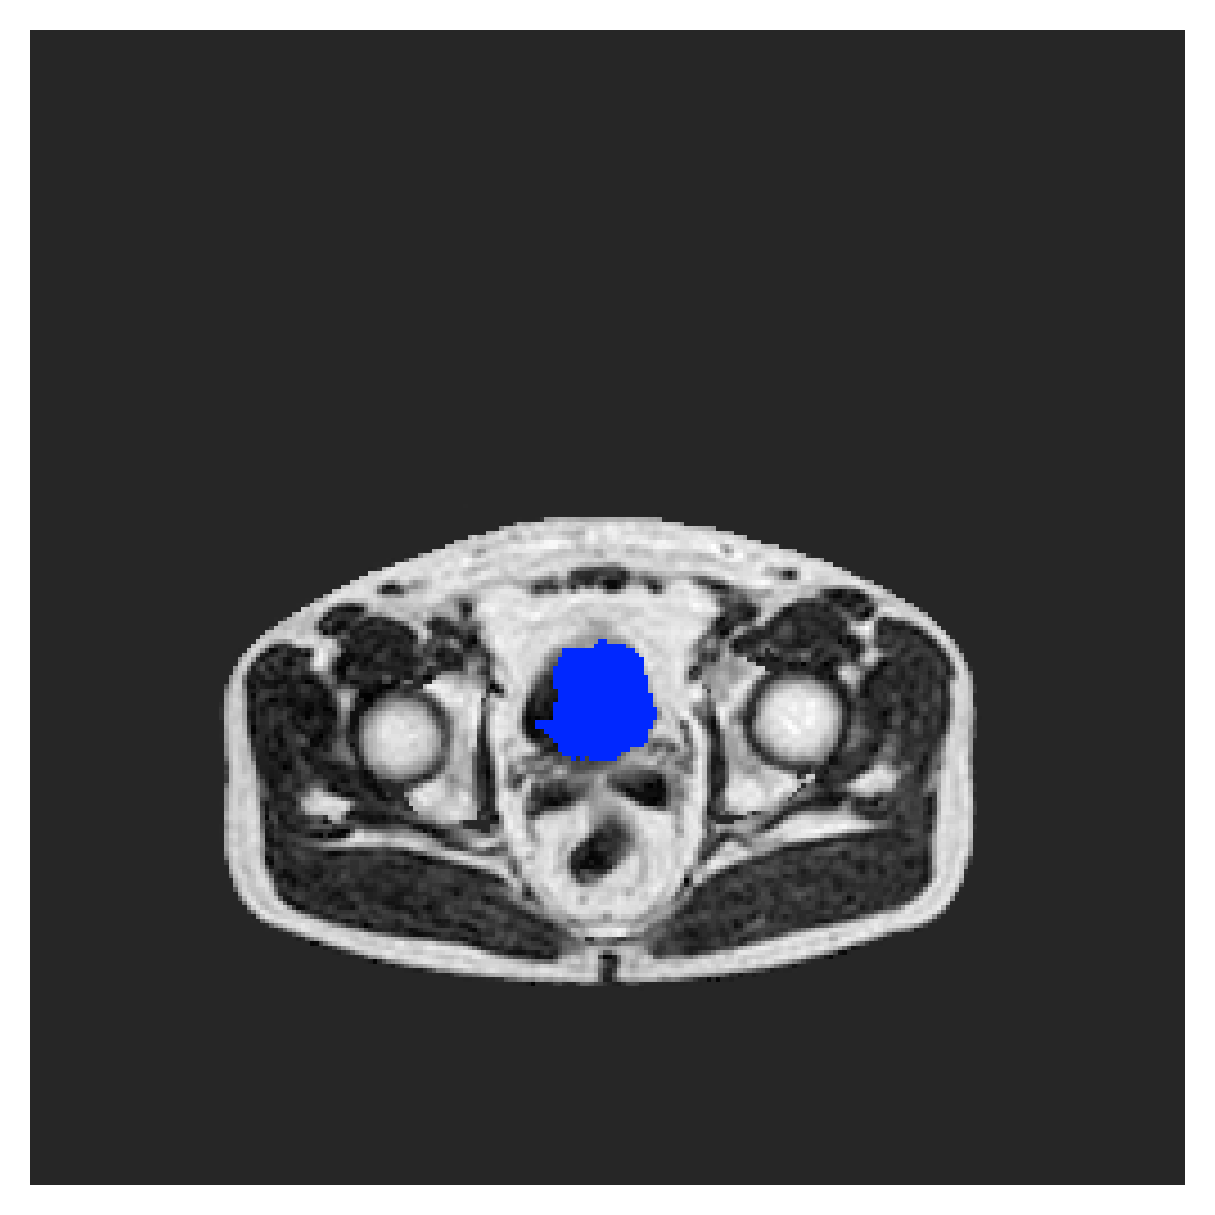

We normalize the volumes and resize the slices to pixels. As the official dataset comes with full annotations, we create a synthetic point ground truth. This is done by first randomly choosing the centers of the point annotations within the class masks, followed by filling an ellipse with axes lengths of and (in pixels) around each center. The intersections of these elliptic discs with the underlying full annotations are then used as our point ground truth. See Figure 2 for an example of the created weak annotation mask. The point annotations are created for every slice, one for each foreground object present in the slice.

Qualitative comparison

|

|

|||

|

|

|

|

|

|

|

|

|

|

|

|

| (a) Ground truth | (b) , full | (c) , weak | (d) |

| (full) | supervision | supervision | |

|

|

|

|

|

|

|

|

|

|

|

|

| (e) | (f) | (g) | (h) CRF-loss |

In Figure 6 we provide qualitative results on a number of randomly chosen test set slices. Upon visual inspection, we can observe that training with the intensity-aware distances (particularly with and ) follows the image gradients better and is better at recovering the underlying shape than the Euclidean version. The CRF-loss seems to recover the shape of the myocardium and left ventricle to some extent, but fails entirely on the right ventricle.